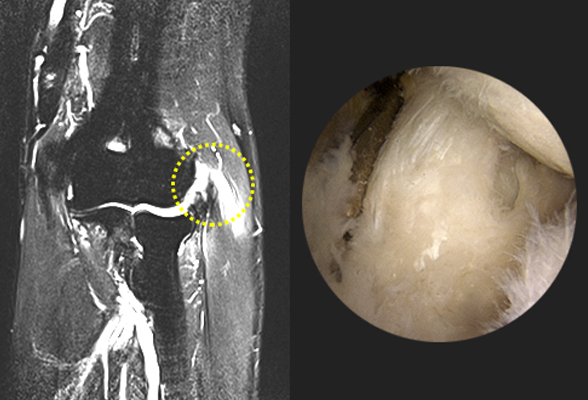

팔꿈치 인대 파열

야구선수들이 던지기 동작이나 운동 중 외상으로 인해 팔꿈치 내측부위의

인대가 늘어나거나 파열되어 관절의 불안정성이 생기는 질환입니다.

비수술 치료 : 고정치료(보조기), 주사 치료, 도수 재활 치료